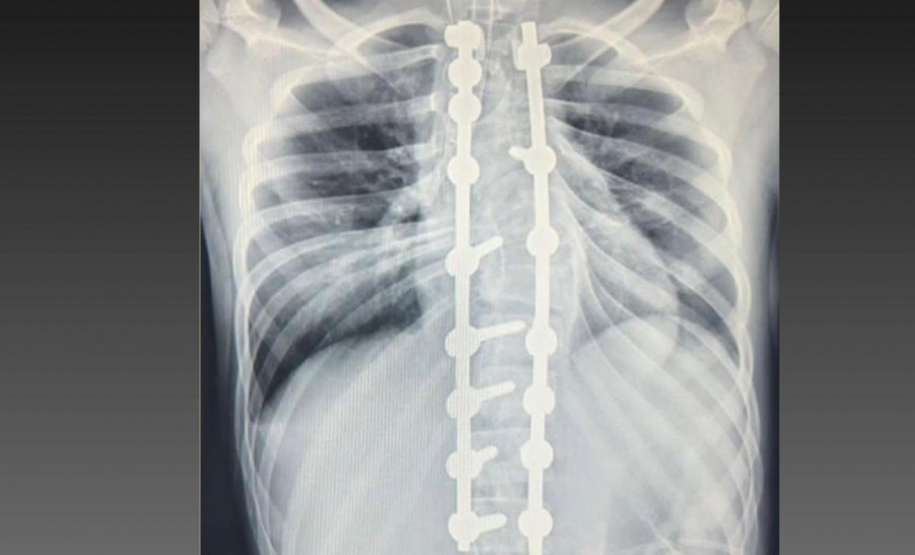

Laura era portadora de escoliose e, em agosto de 2025, realizou a cirurgia de correção da coluna, o que lhe permitirá ter uma vida normal de agora em diante. Moradora de Bom Sucesso do Sul, região Oeste do Paraná, é acostumada a andar a cavalo, mas com o problema na coluna a prática estava longe de ser prazerosa.

Após o atendimento na unidade de saúde da cidade onde reside, foi encaminhada para o Serviço de Deformidades Pediátricas da Coluna Vertebral em Curitiba, onde fez as consultas iniciais e teve a indicação para a cirurgia. Agora, Laura aguarda a alta médica para poder cavalgar e realizar outras atividades sem sentir dores.

A cirurgia ocorreu no dia 28 de julho e uma segunda etapa em quatro de agosto. Desde então, Joyce viu a sua vida mudar. “Nasci com a escoliose e tinha muita dificuldade e limitações para caminhar e perda de movimento. Havia dias em que eu não levantava da cama. Quando saia de casa recebia olhares de julgamento das pessoas, que era o que mais me incomodava. Depois da cirurgia, posso dizer que eu tenho uma nova vida. Eu venci a batalha”, relatou.